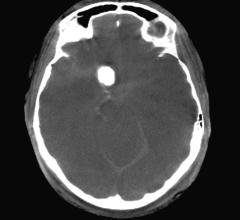

Artificial intelligence (AI) radiology solution provider Aidoc announced the commercial release of its CE-marked product for the identification and triage of pulmonary embolism (PE) in computed tomography (CT) pulmonary angiograms. By flagging obstructions in blood-flow to the lungs, Aidoc prioritizes radiologists’ work queues and helps them detect critical conditions faster, leading to quicker treatment and saving lives.